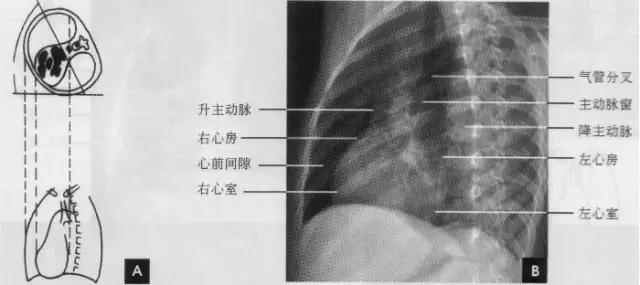

标准右前斜位(又称第一斜位)为后前位向左旋转约45。所得影像。心前缘自上而下由主动脉弓曼升主动脉、肺动脉、右心室漏斗部、右心室前壁和左心室下端构成。升主动脉前缘平直,弓部则在上方弯向后行;肺动脉段和漏斗部稍为隆起;心尖以上大部分为右心室构成。心前缘与胸壁之间有尖向下的三角形透明区称为心前间隙。心后缘上段为左心房,下段为右心房,两者无清楚分界。心后缘与脊柱之间透明区称心后间隙,食管在心后间隙通过,钡剂充盈时显影。右前斜位主要观察右室流出道及左心房大小(如下图)。

(四)左侧位 心影从后上向前下倾斜,心前缘下段为右心室前壁,上段则由右心室漏斗部与肺动脉主干构成,再苣上为升主动脉前壁,直向上走行。这些结构与翦髓壁之间的三角形透亮区称为胸骨后区。心后缘上中段由左心房构成,下段则由左心室构成。心后下缘、食管与膈之间的三角形间隙,为心后食管前间隙(如下图)。